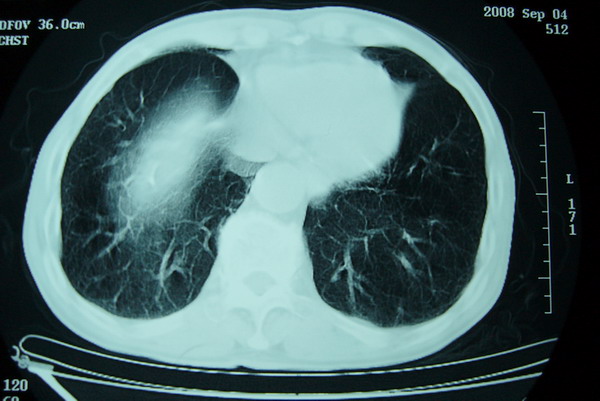

标题: CT15579:男 86岁 咳嗽 咳少量白痰 发热2天 吸烟史60年 [打印本页]

标题: CT15579:男 86岁 咳嗽 咳少量白痰 发热2天 吸烟史60年

右上周围型肺癌,慢支,肺气肿。

分叶及少量边缘性钙化,老年人,周围性肺癌首先考虑。

右肺上叶巨大软组织肿块,轮廓不规则,纵隔内有肿大淋巴结,首先考虑肺癌。

右上肺一不规则团块,边缘有分叶和毛刺,纵隔有淋巴结肿大。右肺周围性肺癌首先考虑。